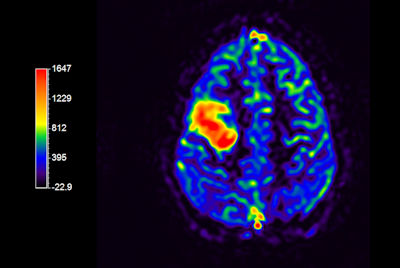

Multi Nuclei - Brain imaging (23Na)